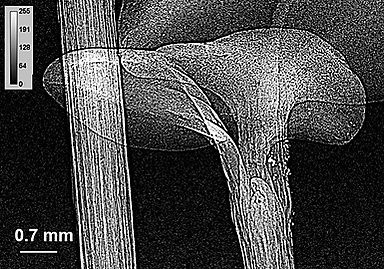

Существуют два типа рентгеновских микроскопов — отражательные и проекционные. В отражательных микроскопах используется явление преломления рентгеновских лучей при скользящем падении. Проекционные микроскопы используют высокую проникающую способность рентгеновских лучей. В них изучаемый объект помещается перед источником излучения и просвечивается рентгеновскими лучами. Благодаря тому, что коэффициент поглощения рентгеновских лучей зависит от размеров атомов, через которые они проходят, такой метод позволяет получать информацию не только о структуре, но и о химическом составе изучаемого объекта.

Проекционные рентгеновские микроскопы представляют собой камеру, в противоположных концах которой располагаются источник излучения и регистрирующее устройство. Для получения чёткого изображения необходимо, чтобы угловая апертура источника была как можно меньше.

Проекционные микроскопы получили широкое применение в различных сферах науки, включая медицину, минералогию, металловедение.

- получить микрорентгенографии биологических и ботанических срезов толщиной до 200 мкм.